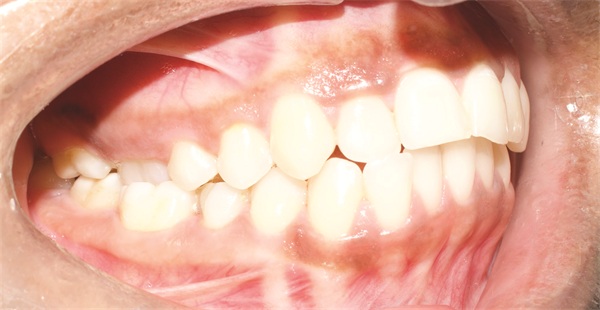

The diagnostic findings told a more complicated story. The patient presented with a skeletal Class II relationship, bilateral Class I molar and canine relationships, collapsed arches, and proclined incisors in both arches. Both midlines were shifted to the right. She also exhibited crossbite of the upper right first molar and upper right lateral incisor, a discrepancy between centric relation and centric occlusion, and a noticeable cant in the lower anterior segment. Her dental history included previous extractions of the upper right third molar and upper left second molar (Figs. 1–12).

Fig. 2